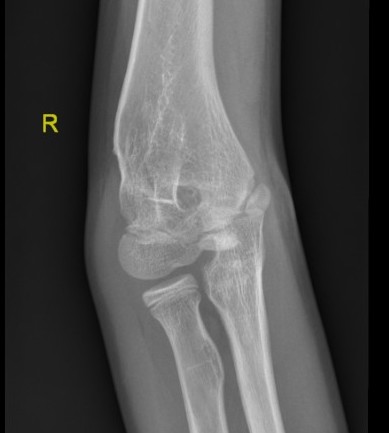

Lateral Xray

Position for good lateral

- thumb vertical

- hand above elbow

Anterior angulation

- shaft - condylar axis

- normally 40o

Lines

Anterior humeral line (AHL)

- should pass through middle of capitellum

Radio-capitellar line

- pass through capitellum

Teardrop

- shadow above the capitellum

- anterior dense line: posterior margin of the coronoid fossa

- posterior dense line: anterior margin of the olecranon fossa

- inferior portion: ossification center of the capitellum

AP X-ray

Baumann's Angle

Technique

- angle between longitudinal axis humerus and capitellar physis

- should equal uninjured side

- 75o normal

Cubitus varus

- varus malposition > 81°

Cubitus valgus

- < 70o